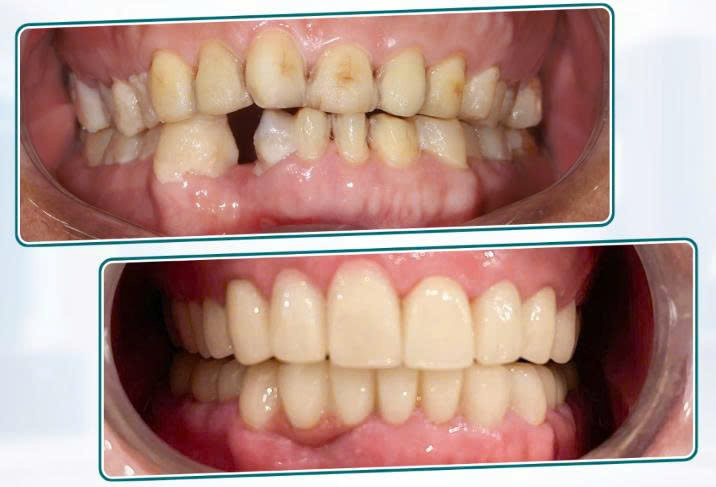

6 Kết quả sau điều trị – So sánh trước & sau

6.1 Về chức năng

-

Cảm giác đau nhức chấm dứt

Khả năng ăn nhai cải thiện rõ rệt

Khớp cắn ổn định, không còn cảm giác mỏi hàm

6.2 Về thẩm mỹ

Hàm răng đều, màu sắc tự nhiên

Hình thể răng hài hòa, phù hợp khuôn mặt

Nụ cười tự tin hơn, trẻ trung hơn